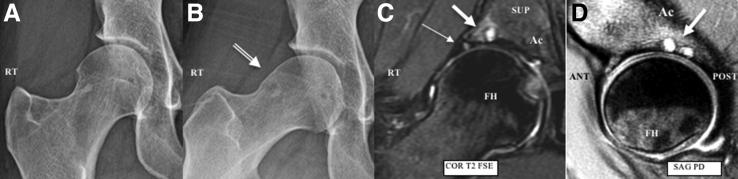

Intraosseous bioplasty (IOBP), has been previously described for arthroscopic-assisted treatment of subchondral bone cysts in the proximal tibia associated with early stages of knee osteoarthritis (OA). This technique entails combining bone marrow aspirate concentrate or concentrated platelet-rich plasma with demineralized bone matrix as a bone substitute before injecting into a subchondral bone defect under fluoroscopic guidance. The principles of IOBP as a procedure that combines core decompression with biologic bone substitute augmentation can be extended to treat subchondral bone marrow lesions such as acetabular and femoral cysts in degenerative hip OA. Intraosseous bioplasty of the hip, in particular the acetabulum, when done using this technique, is a useful alternative that can be beneficial in treating young patients with early hip arthritis to achieve successful outcomes while delaying more invasive procedures. The Technical Note described here presents a step-by-step approach, including tips and pearls for arthroscopic-assisted IOBP with decompression of the subchondral cyst in the acetabulum followed by bone substitute injection under fluoroscopic guidance. We believe this method is a safe and reproducible way to treat subchondral defects in young patients with signs of early osteoarthritis of the hip joint.

摘要

骨内生物成形术(IOBP),此前已被描述用于关节镜辅助治疗与膝关节骨关节炎(OA)早期相关的胫骨近端软骨下骨囊肿。该技术需要在透视引导下将骨髓抽吸浓缩物或富含血小板的浓缩血浆与脱矿骨基质作为骨替代物混合,然后注入软骨下骨缺损处。IOBP作为一种将髓芯减压与生物骨替代物增强相结合的手术方法,其原理可扩展至治疗退行性髋关节OA中的软骨下骨髓病变,如髋臼和股骨囊肿。使用该技术进行髋关节,尤其是髋臼的骨内生物成形术,是一种有用的替代方法,对治疗早期髋关节关节炎的年轻患者有益,可在延迟更具侵入性的手术的同时取得成功结果。此处描述的技术说明介绍了一种逐步方法,包括关节镜辅助IOBP并对髋臼软骨下囊肿进行减压,随后在透视引导下注射骨替代物的技巧和要点。我们认为该方法是治疗有早期髋关节骨关节炎迹象的年轻患者软骨下缺损的一种安全且可重复的方法。